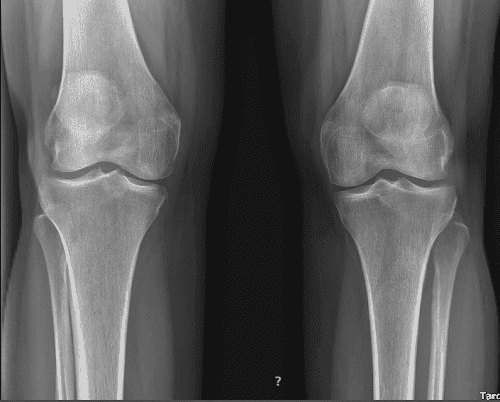

She takes Tylenol which helps. X-ray result presented today and it clearly showed her bilateral knees have mild patellofemoral compartment osteoarthritis and small joint effusion.

Patient returned to our office a week after the initial visit. Presented bilateral X-rays. Left knee demonstrates small full-thickness cartilage defects of the medial with inferior aspect of the lateral patellar facets with underlying patchy subchondral bone marrow edema.

Small partial-thickness cartilage defects on the medial trochlear facet. Small partial thickness cartilage loss central aspect of the medial femoral condyle with underlying small faint subchondral bone marrow edema. Small joint effusion and intact cruciate and collateral ligaments.

Her MRI right knee showed impression as follows: full-thickness cartilage defect inferior aspect of the lateral patellar facet and small full-thickness cartilage fissures of the medial patellar facet with underlying subchondral bone marrow edema.

Small full-thickness cartilage fissure of the medial trochlear facet with underlying small subchondral edema. Small full-thickness cartilage defects central aspect of the medial femoral condyle with underlying small subchondral bone marrow edema. Small to moderate joint effusion. Trace popliteal cyst.